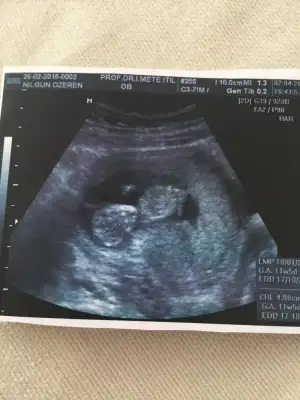

Ay ben kızım usglerine bakıyorum baya baya belliymiş bacak arası boş bende 20.haftaya kadar cinsiyet beklemişim😂 şimdiki bilgim ozaman olaydı yorum yapabilirmişim🤣

Iste bende dolu gordum ama neye göre bilemedim resim çekseydim keske neyse yarın gorcez😁